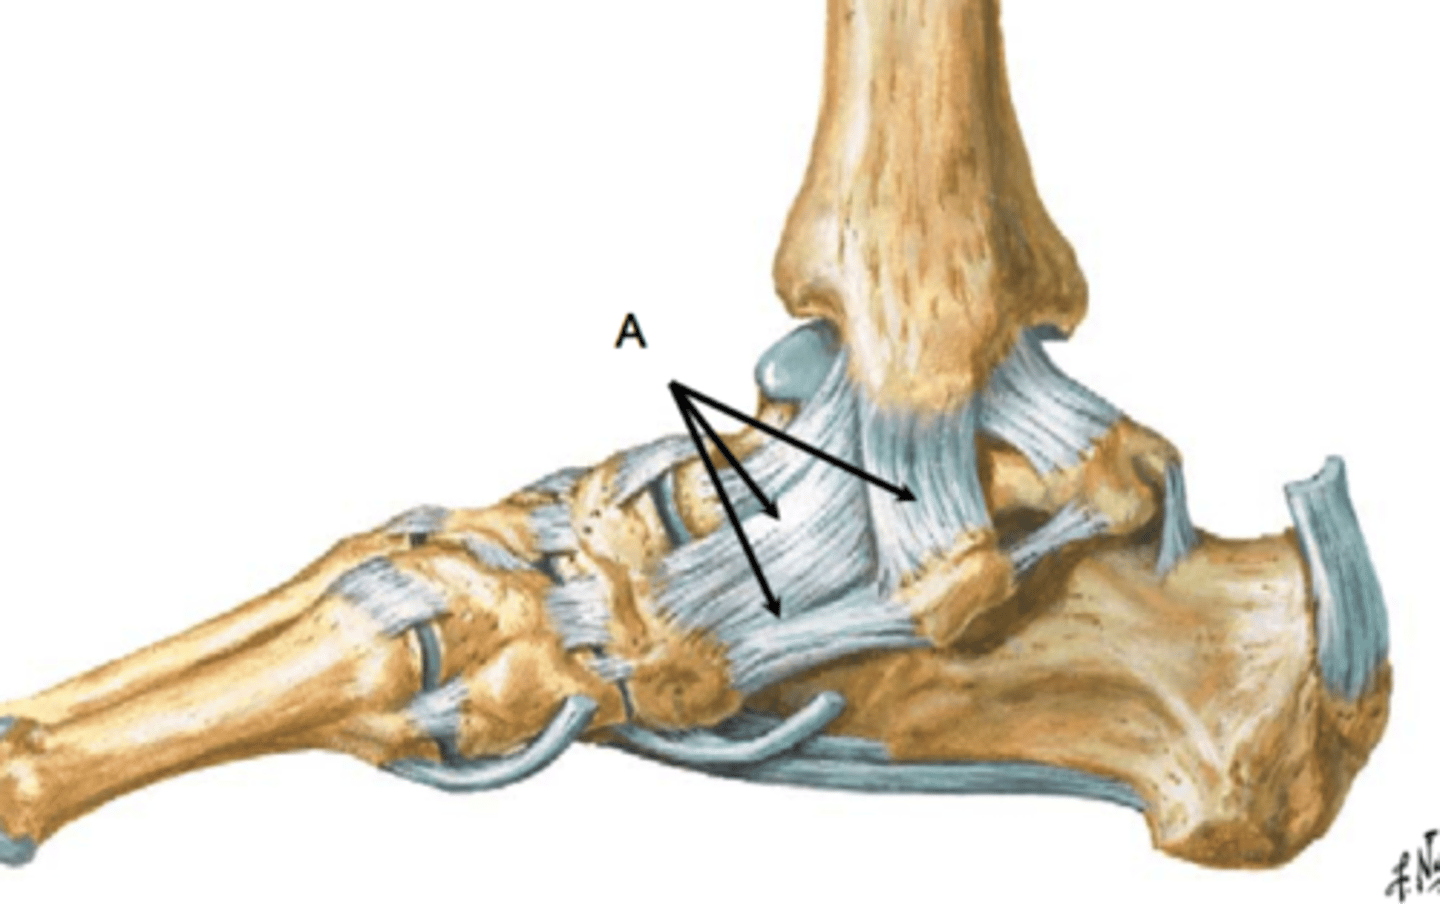

What is the medial ligament of the ankle?

deltoid ligament

Composed of:

- anterior tibiotalar

- tibionavicular

- tibiocalcaneal

- posterior tibiotalar